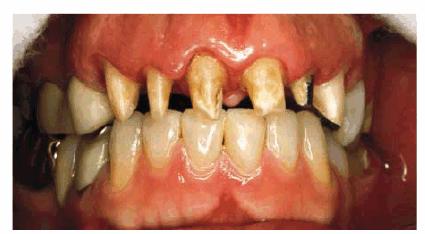

PROBLEM: This 38-year-old store owner presented with crowded and

discolored maxillary and mandibular teeth (Figures 24-7A, and 24-7B). Although orthodontic treatment was suggested as ideal

treatment, he elected a compromise that consisted of bonding the mandibular and

Figure 24-7A: This 38-year-old man wanted to improve his crowded maxillary and mandibular teeth.

Figure 24-7B: This occlusal view shows why full orthodontic treatment was originally presented as the ideal treatment. The patient insisted on a "quick fix" solution.